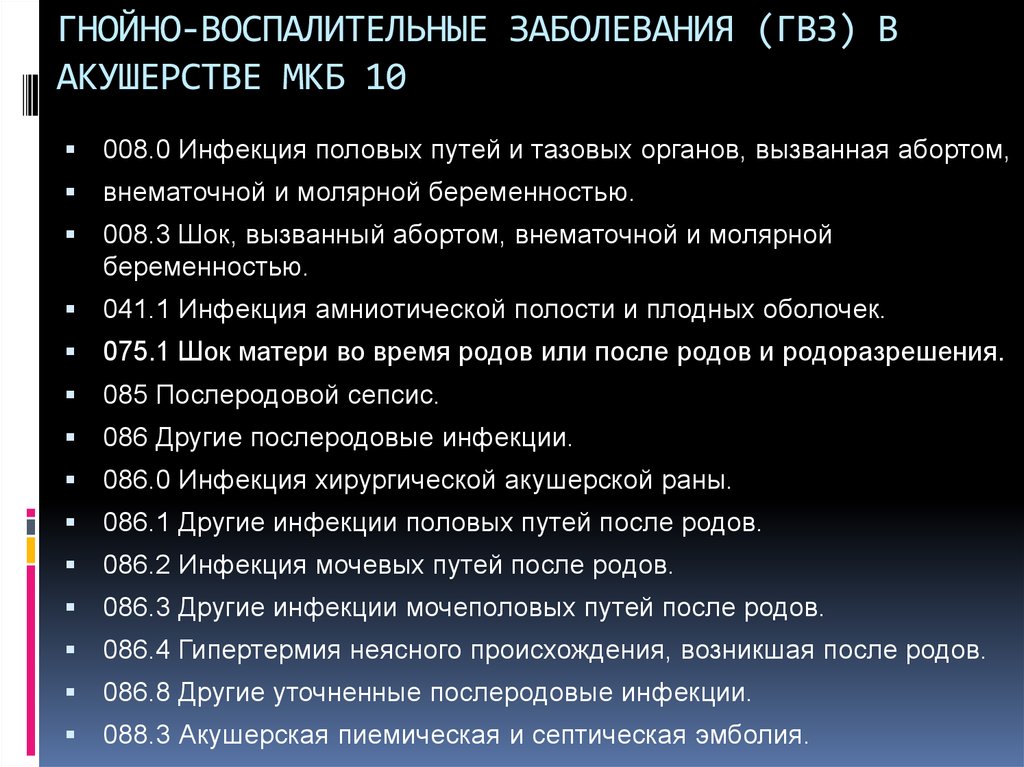

Код мкб 10 атерома головы

Код мкб 10 атерома головы 109 фото